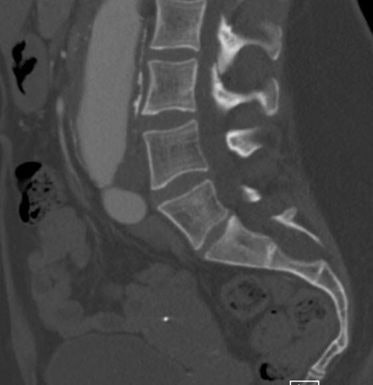

Dural ectasia. One of the most specific skeletal findings is lumbosacral dural ectasia, a ballooning or widening of the dural sac. It is best visualized on MRI of the lumbosacral spine and is considered a major diagnostic criterion in the revised Ghent nosology.

Same 39-year-old woman from above. More inferiorly dural ectasia can be seen with posterior scalloping of the sacrum typical of Marfan syndrome.